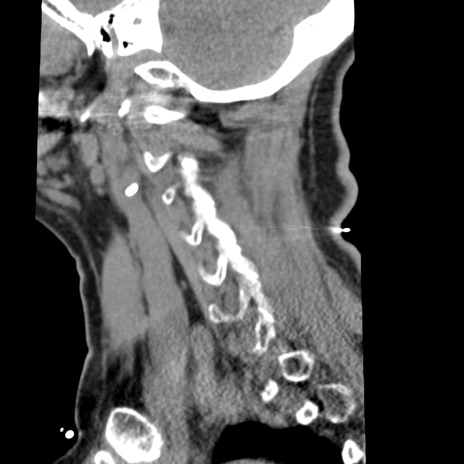

症例50 頚椎CT(矢状断像)

【症例】60歳代女性

【主訴】後頭部〜右後頸部にかけての痛み

【現病歴】本日飲食店でコーヒーを飲んでいたところ、突然後頭部〜右後頸部にかけて痛みが出現し、右上肢の感覚障害を伴ったため救急要請。

【身体所見】脳神経学的に明らかな異常所見を認めず。右上肢に軽度の感覚障害あり。

頚椎CT